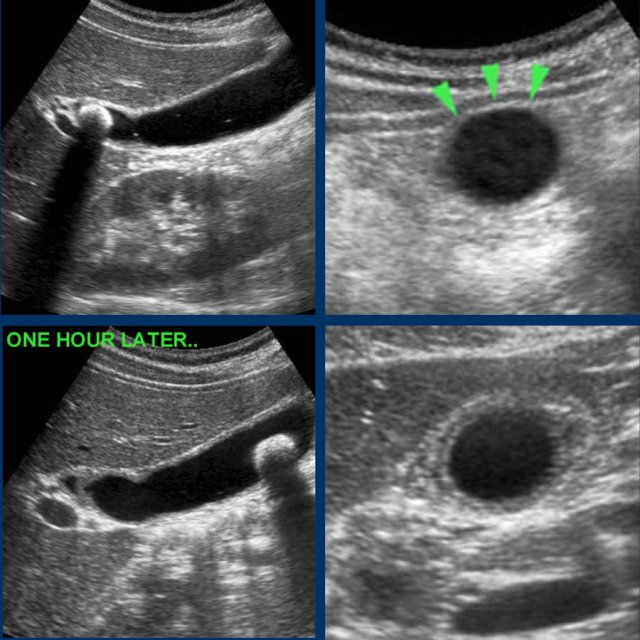

Images of a young woman with a biliary colic for 8 hours.

US shows an impacted stone and hydrops.

The patient went walking for an hour and US was repeated.

The stone was loose, and reperfusion edema was visible as silent witnesses of the colic.

CRP remained normal.